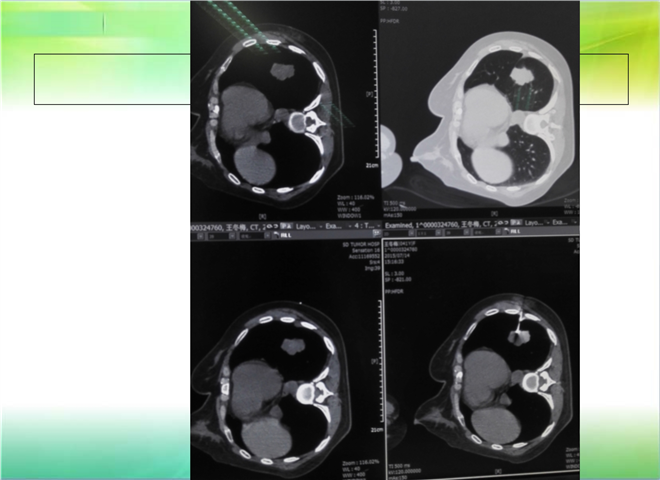

CT引导下穿刺活检术